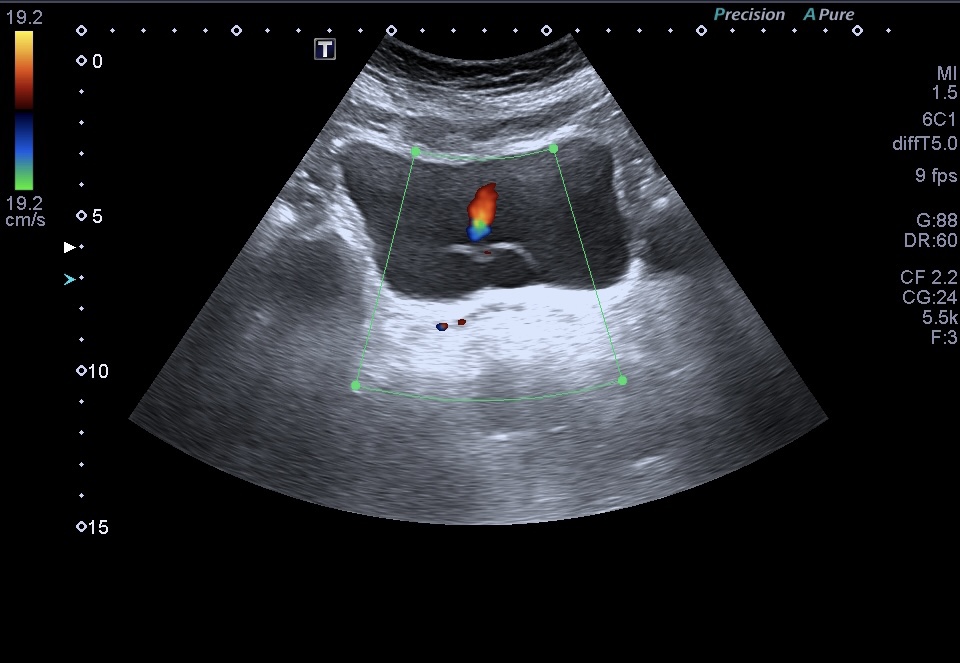

1. Vascularización: La evaluación de la vascularización del urotelioma mediante el registro Doppler es crucial. La presencia de flujo sanguíneo dentro de la masa tumoral, representado por colores en el Doppler, sugiere un mayor riesgo de malignidad.

Vascularización positiva

La vascularización es un hallazgo considerado línea roja.

Se recomienda el uso de Doppler Power para detectar vascularización lenta.

Doppler pulsado presente